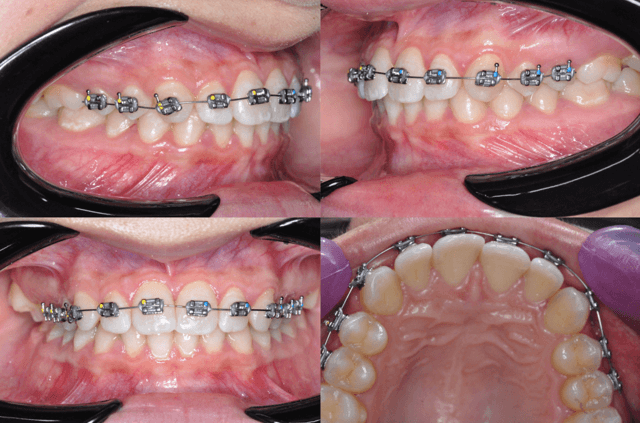

25 de octubre de 2024 (figura 10)

Se realizó ajuste clínico en ambas arcadas, manteniéndose los arcos. Se cementó nuevamente el tubo del órgano dentario 36 el cual se había despegado.

25 de marzo de 2025 (figura 12)

Se reemplazaron los topes anteriores por unos nuevos de menor tamaño. Se cementó un botón lingual en el órgano dentario 47 (OD 47) y uno vestibular en el 17 (OD 17). Se mantuvieron los arcos activos. Se indicaron elásticos cruzados de 1/8" de 2.5 onzas, conectando el botón del 47 con el del 17.

Figura 11. Ajuste.

Figura 12. Ajuste.